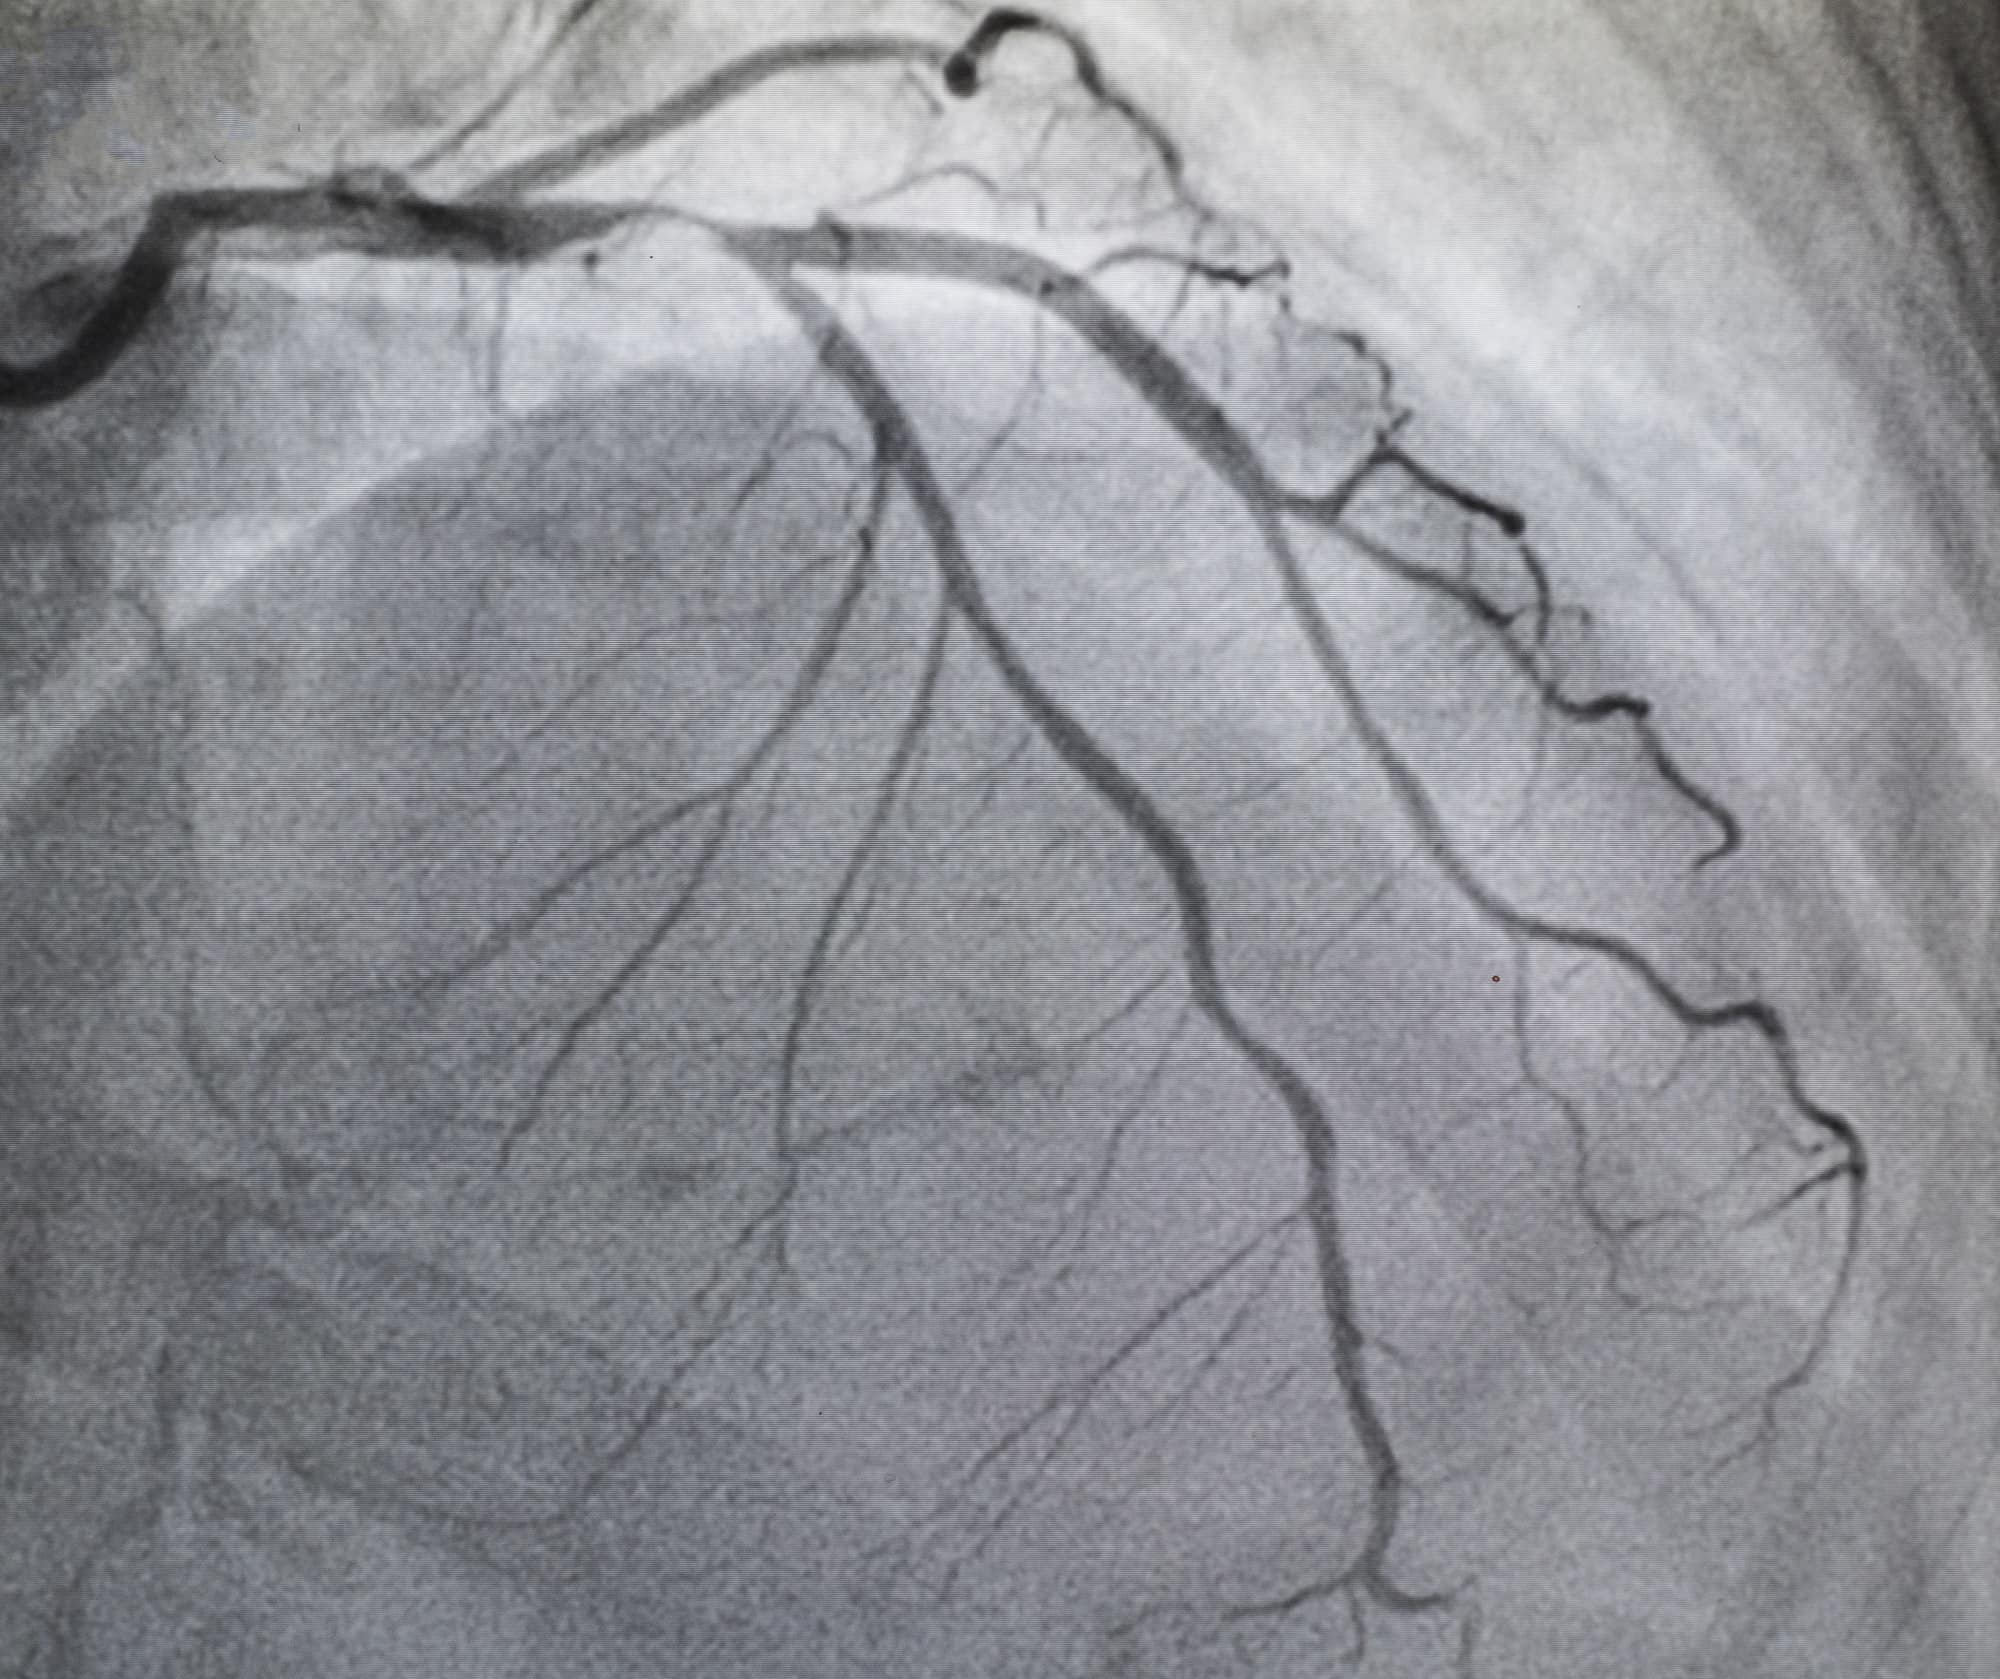

Cost of Angiography should be anywhere between ₹12000/- to ₹18000/-...